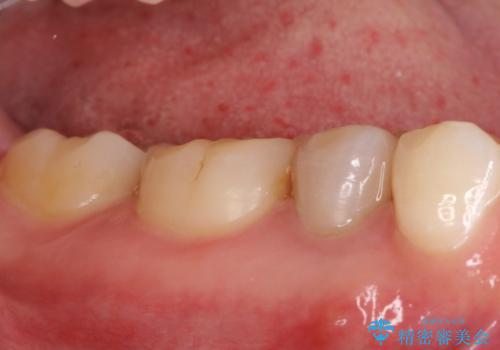

湾曲根管。精密根管治療

湾曲根管に対してエラーなく処置を行えております。